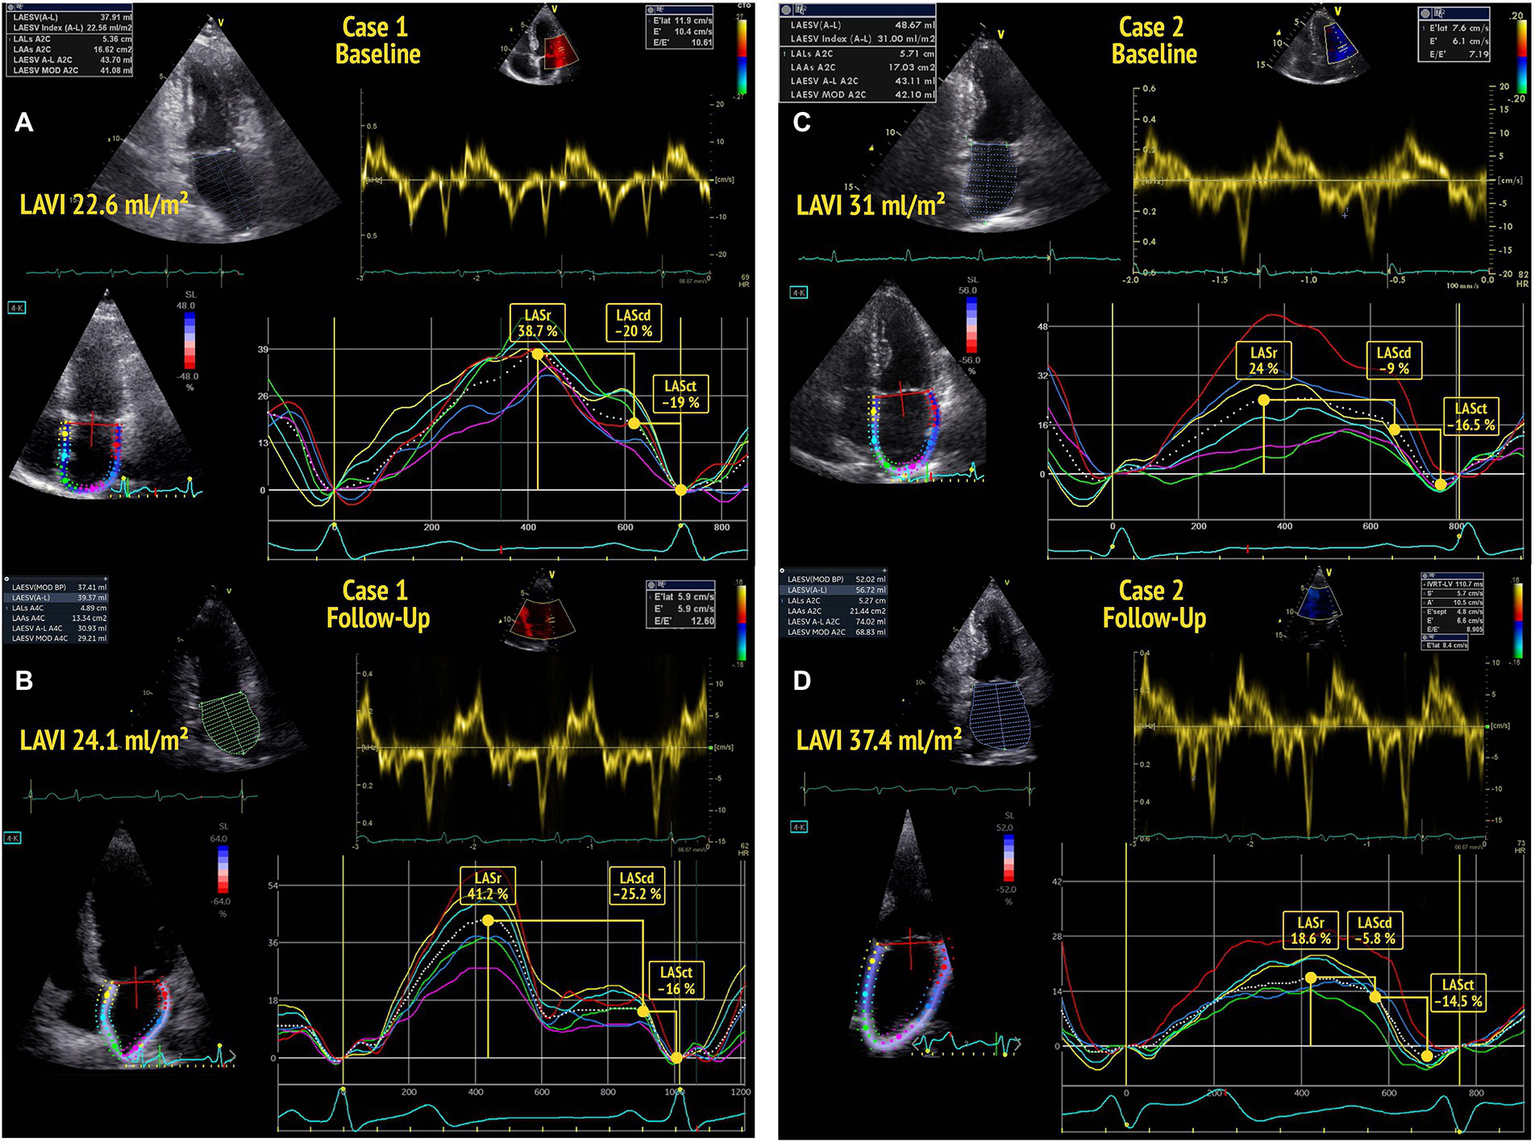

2D STE strain studies were analyzed offline using the EchoPAC v203 software (GE Healthcare). Global peak systolic longitudinal LV strain (LV GLS) was determined from apical 4-chamber, 2-chamber, and long-axis views (17 segment LV model). Phasic LAS was assessed as proposed by the recent EACVI recommendations (12) from an LA focused apical 4-chamber-view, avoiding foreshortening. Three cardiac cycles were recorded for each view and stored for offline analysis. Gain, depth, and frame rate (60–80 frames/s) were optimized for image acquisition. The region of interest was placed on the atrial walls, distributing the interatrial septum and atrial free wall into six segments. LAS was analyzed QRS-triggered. LASr was identified from the plotted average strain curve as the maximum amplitude during ventricular systole. LA conduit strain (during passive LV filling; LAScd) and LA contraction strain (during peak atrial contraction; LASct) were calculated from the generated strain curve as previously described (4, 12, 22) (Figure 1).

Figure 1

Baseline echocardiography of two participants (A,C) showing normal left atrial volume index (LAVI) (<34 ml/m2) and normal diastolic function according to the 2016 ASE guidelines. The participant in A shows a left atrial reservoir strain (LASr) >34% at baseline and no deterioration of diastolic function by the time of follow-up (B). The participant in C presents with a low baseline LASr and shows a decline of diastolic function (DD0 to DD1) by the time of follow-up echocardiography (D).